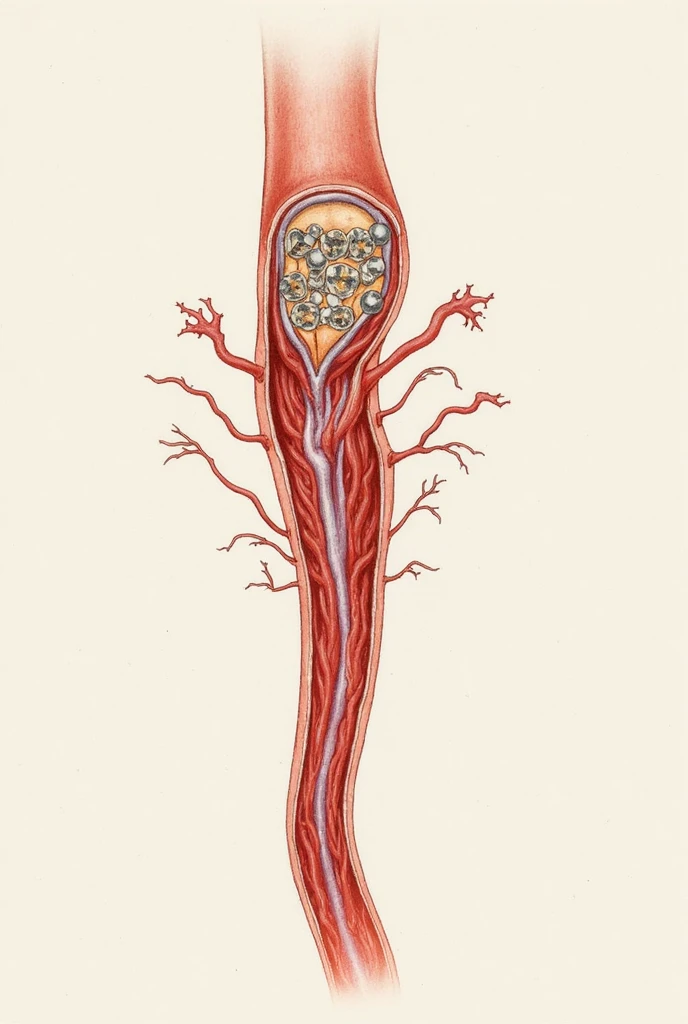

Realice un dibujo de la piel. Coloque las siguientes referencias: Epidermis Fermis Hypodermis Keratinized squamous stratified epithelium Hair Sebaceous gland Sweat gland Pilo erector muscle Connective tissue Blood vessels Nerves Adipocytes

Epidermis Fermis Hypodermis Keratinized squamous stratified epithelium Hair Sebaceous gland Sweat gland Pilo erector muscle Connective tissue Blood vessels Nerves Adipocytes